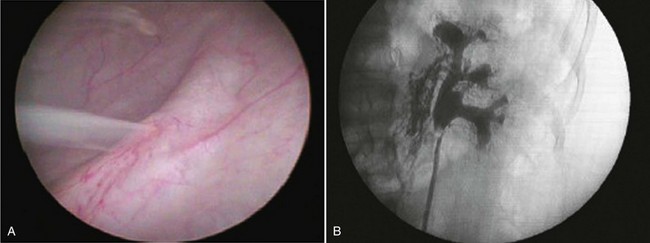

Patients typically present with milky white urine and may have nephrotic range proteinuria. Initial evaluation includes urinalysis and culture, urine for chyle, and complete blood count to check for eosinophila. Evaluation to localize the fistula may include cystoscopy with retrograde pyelogram, CT, magnetic resonance imaging (MRI), or lymphangiography (Fig. 55–30).

Chyluria is often self-limited, and many patients may be managed conservatively. In filariasis-associated cases, this involves treatment with a course of diethylcarbamazine (DEC) in combination with a low-fat diet (Tandon et al, 2004). Retrograde instillation of silver nitrate or povidone iodine into the collecting system as a sclerosing agent has also been described, and these agents are commonly used as first-line treatment with comparable success rates of approximately 80% (Dalela et al, 2004a; Goel et al, 2004). When conservative management fails or if cases are particularly severe, surgical intervention is undertaken.

Nephrolysis involves the complete mobilization of the kidney and skeletonization of the renal hilar vessels and upper ureter with ligation of the lymphatic channels. The procedure may be performed laparoscopically by either a transperitoneal or retroperitoneal approach and ensures complete lymphatic dissociation of the affected kidney (Chiu et al, 1995, Gomella et al, 1998). The use of an omental wrap around the hilum has also been described to provide an additional barrier against recurrence (Dalela et al, 2004b). Authors commonly performing this procedure report excellent success rates—approaching 100%.